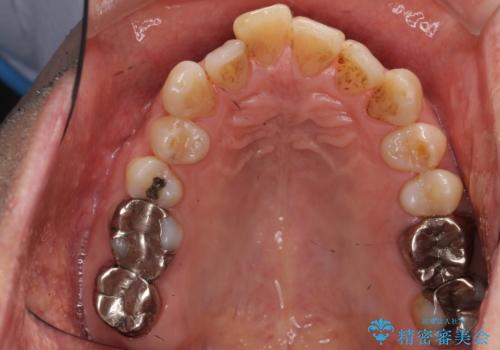

奥歯がわれている ソケットリフトを併用した奥歯のインプラント 60代男性

- 奥歯が咬むと痛い、熱いものがしみることを主訴に来院された患者様です。

奥歯(左上7)のメタルインレー(銀の詰め物)を除去し精査したところ、奥歯はわれていました。

根尖近くまで深くヒビが入っており保存不可能な状態でした。